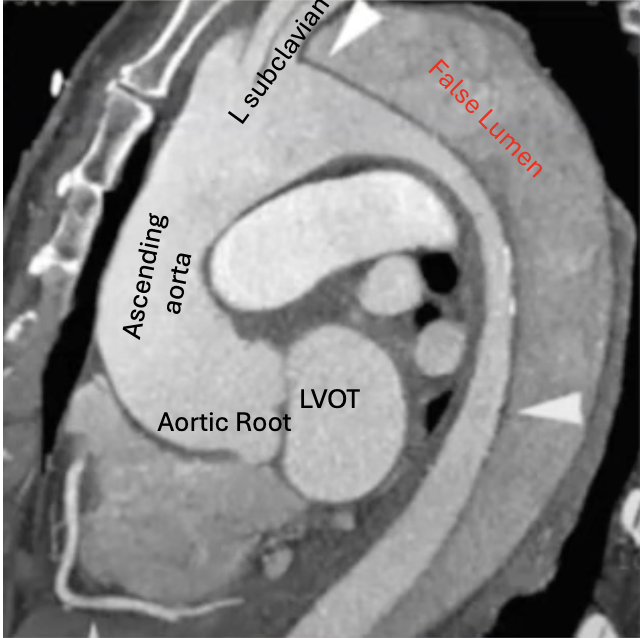

🚨 Answer revealed 🚨 This sagittal CTA shows a Type B aortic dissection 🩸 Intimal flap distal to the left subclavian artery → classic setup. 🧠 Why it matters: • Medical management first (BP & HR control) • Endovascular intervention if complications arise #RadTwitter

0

1

5

🫀Cardiac imagers save lives. 🧠 High-stakes anatomy and management hinges on exactly what this represents. What’s the diagnosis—and what’s your next move? 👇 Drop your call below #RadTwitter #Radiology #Radres #Cardiology #ImagingPearls

7